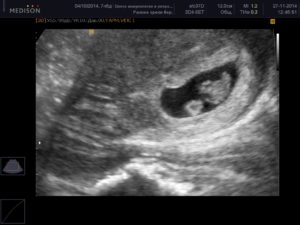

Объективным сроком, на какой неделе визуализируется два плода, считается пятая неделя с момента зачатия. На экране монитора ультразвук показывает два темных пятна в маточной полости. По мере формирования малышей картинка будет меняться. Когда детей двое, они, как правило, немного отстают по фенометрии (определение размеров посредством УЗИ).

Следовательно, наличие двойняшек в утробе выявляется посредством ультразвука уже через месяц после зачатия, на снимке они выглядят как 2 образования темного цвета внутри полости матки (см. фото УЗИ-обследования двойни ниже).

Увидеть двойню на УЗИ при беременности можно уже через месяц после зачатия. В этом случае специалист отметит на экране монитора два пятна черного цвета, которые хорошо просматриваются ультразвуком